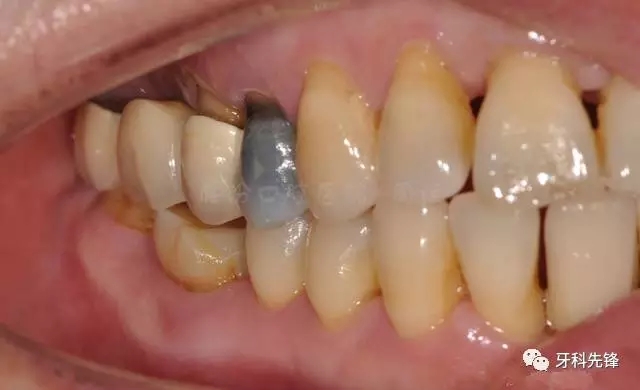

圖5拆除原修復(fù)體側(cè)位咬合照